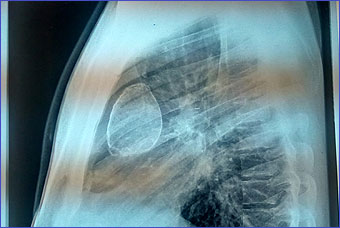

Case 1

A 30 years old male presenting with low grade fever and cough with scanty mucoid expectoration and streaky hemoptysis for last one year. His complaints was subsided with oral co amoxiclav and cough suppressant. He has no chest pain or shortness of breath. Past history revealed tubercular pleural effusion at 4 years of age with ATD completed then. He remained asymptomatic for last 26 years. His chest x-ray and CT scan chest given. Mantoux test is positive showing 10mm induration. His echinococcus IgG is positive in high titre.